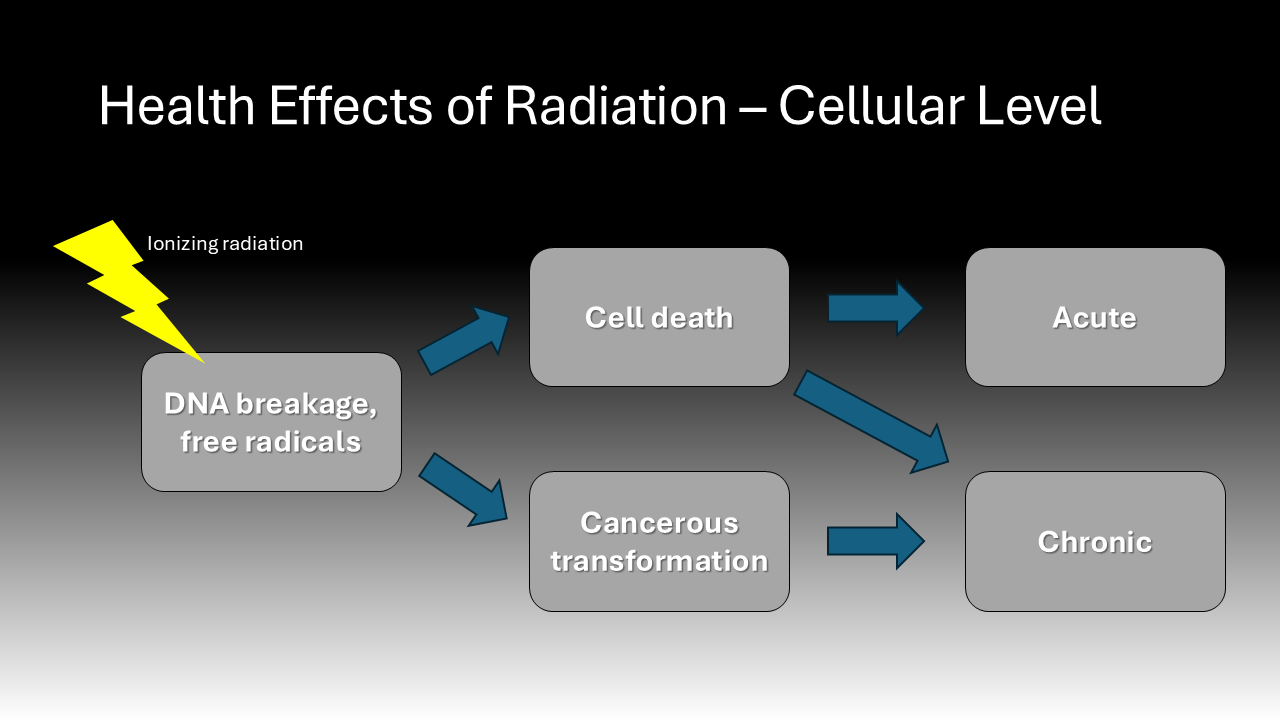

The health effects of radiation exposure have been known since the immediate years following the introduction of X-ray technology when there was noted to be an increase in incidence of cancers among workers.11 More recent molecular research elucidates the mechanism by which radiation leads to deleterious effects. Ionizing radiation causes DNA breakage and mutation directly and through the generation of free radicals.11 One study found that molecular markers of DNA damage and repair were increased among the lymphocytes of patients and hospital staff immediately post-operatively when fluoroscopy was used.12 This resulting genetic instability may either kill a cell or cause it to become cancerous.12 The clinical effects of radiation exposure depend on the dose and duration of exposure. High doses can lead to severe skin damage and acute radiation syndrome, almost all exposure in healthcare involves low doses over long periods.4 While chronic exposure to low doses of radiation can lead to non-cancer effects such as dermatitis, cataracts, and infertility, the focus of this paper is on the cancer effects.6 Most quantifications of cancer risk due to radiation derive from studies on the impact of atomic bombs. Data from Hiroshima and Nagasaki, Japan, demonstrated that radiation exposure increases the risk of a variety cancer types, specifically skin, thyroid, brain, and blood cancers.7 Data from survivors of the atomic bombs was extrapolated to estimate that an exposure of 10 mSv confers a 1 in 2,000 risk of developing cancer of any origin.7 Studies of radiologists in the 1950s further substantiated the link between radiation exposure and the previously mentioned cancer types.13